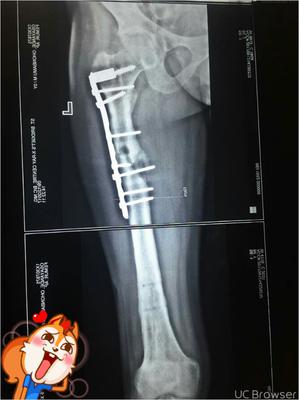

that is my femur.

Muscle weakness, tingling, burning. Had a surgery for my broken femur sometime ago. About a year now. My femur has not healed and I am passing through what I mentioned. The problem started from when I tried to make my stiff knee flexible. I think it affected the fracture site. I am in so much pain for the past 7 months and the doctor is saying nothing about it.

I'm afraid this is an orthopaedic problem, and outside of my domain. The hip doesn't look good either.